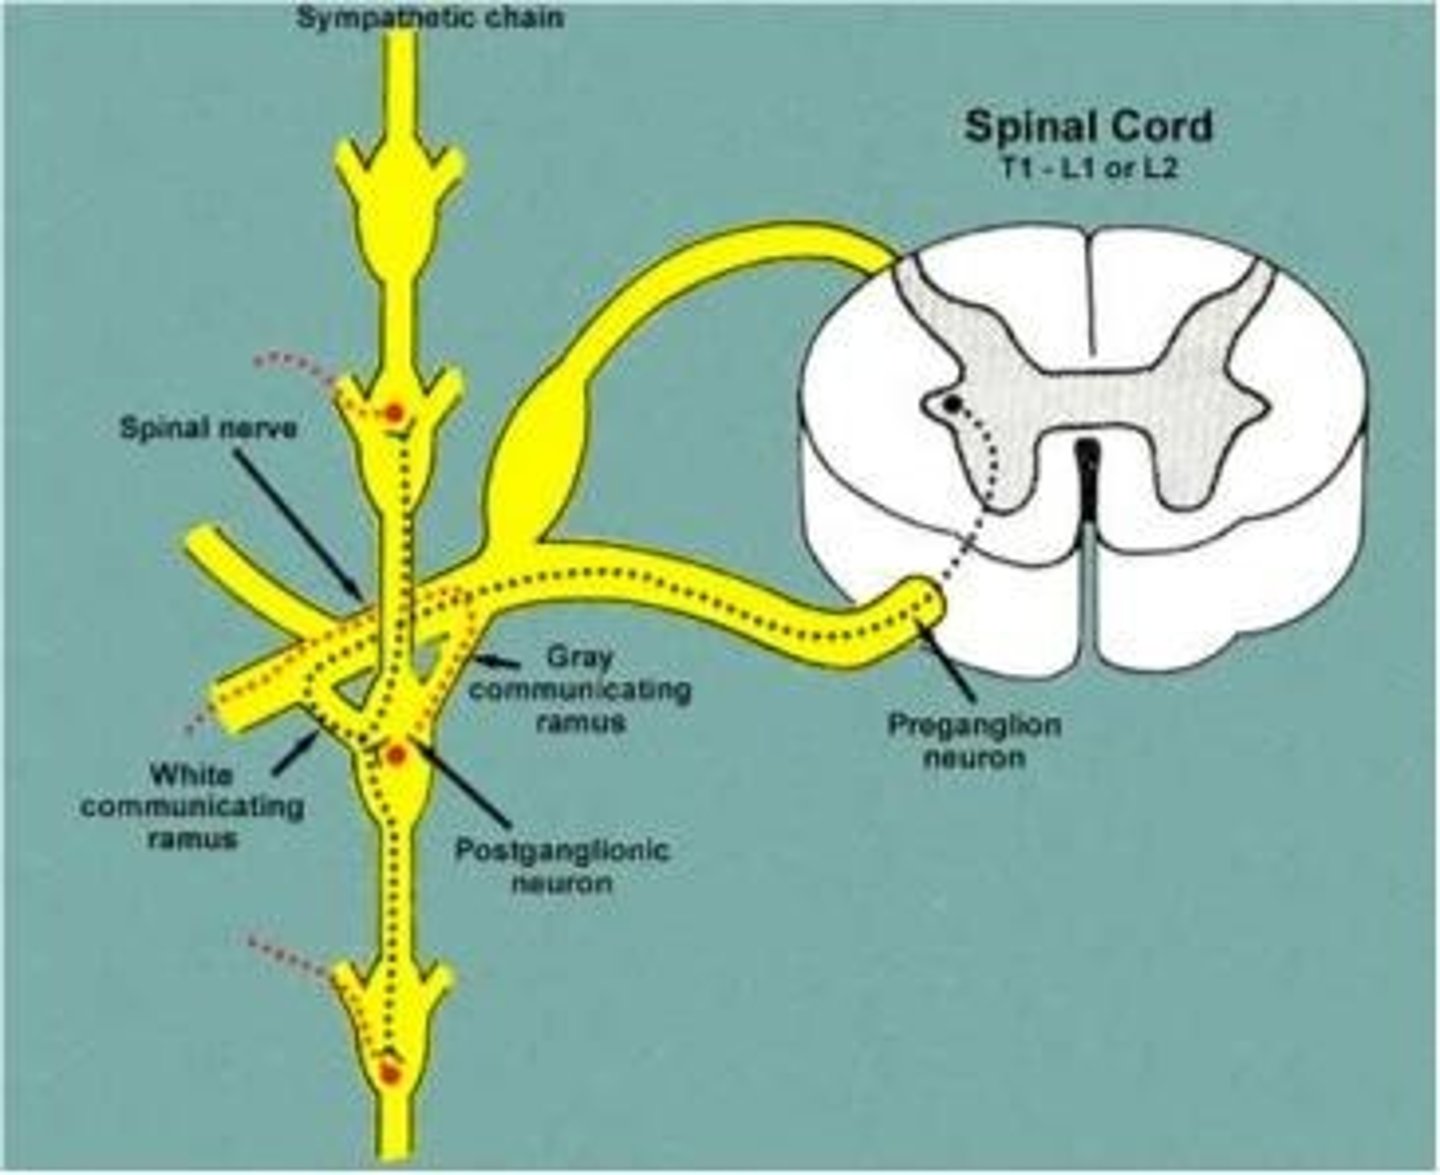

sympathetic trunk/chain ganglia

Runs along vertebrae, part of the sympathetic nervous system, keeps whole body in sync

White rami communicans

contain myelinated preganglionic fibers traveling to sympathetic trunk ganglia

gray rami communicans

contain unmyelinated postganglionic fibers traveling from ganglia to peripheral structures